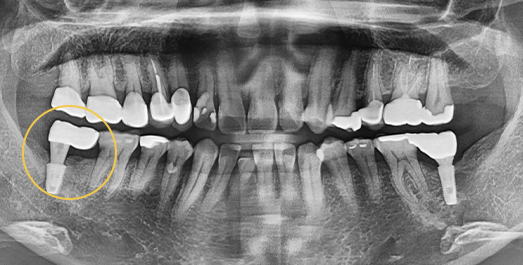

• BEFORE: 2022.12.15

• AFTER: 2023.02.23

Full-Mouth Implant Restoration

Implant treatment for comprehensive full-arch restoration

This implant option is chosen to fully restore dental function. When missing teeth have been left untreated for an extended period,

the alveolar bone volume in both the maxilla and mandible is often insufficient. Therefore, a precise surgical plan must be established

with careful consideration of each patient's overall health condition.